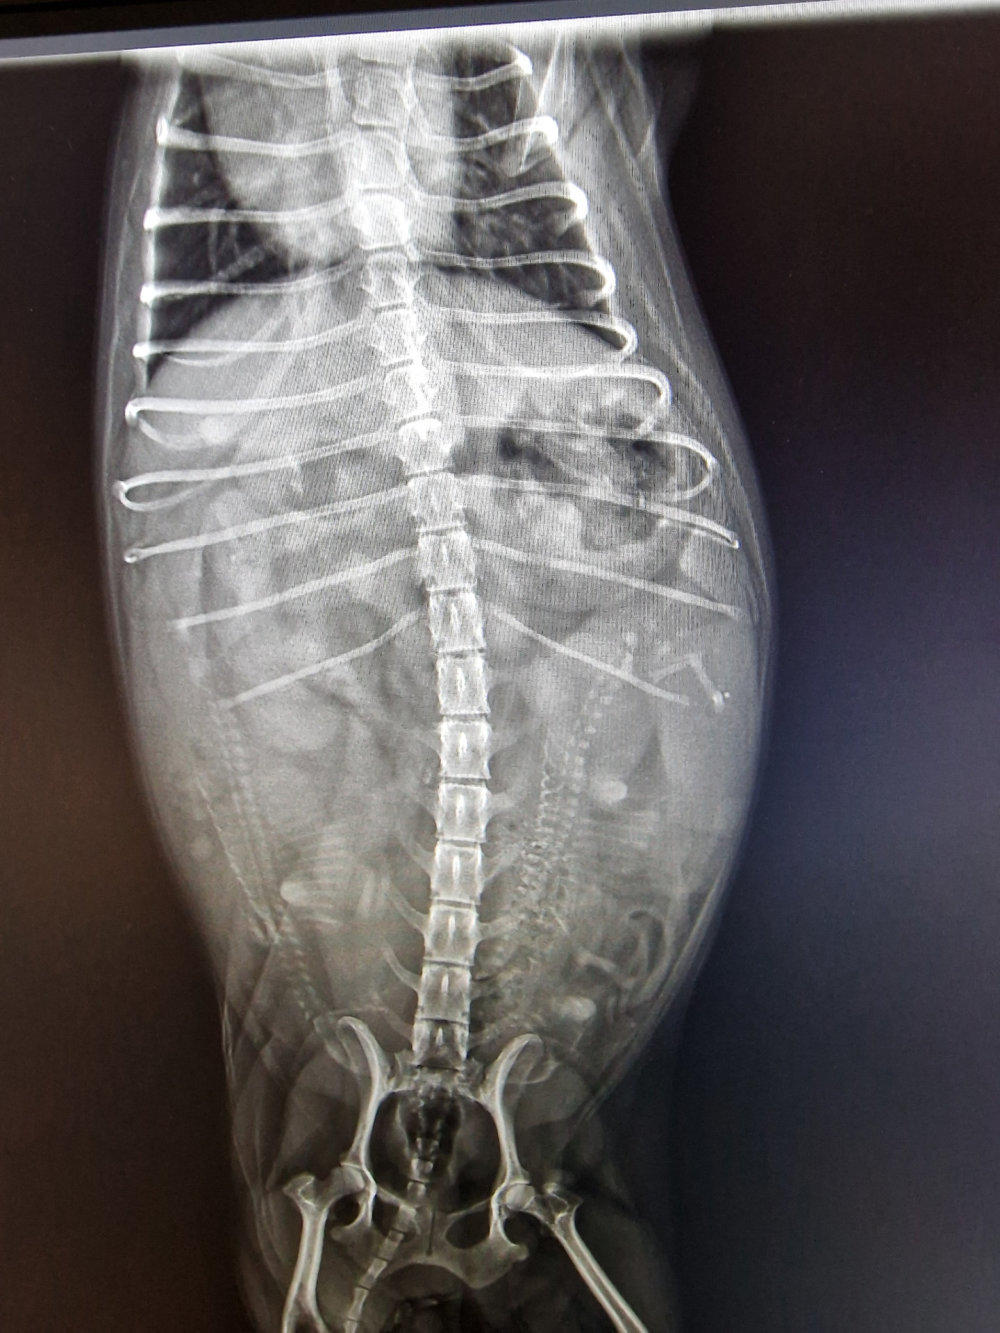

So, heute Morgen war unser Frauli auch mit den anderen drei Mädels zum Röntgen. Im Laufe der nächsten Woche kommt richtig Leben in unsere Bude. Hi, hi. (Röntgenbilder Yule, Lotta und Gina v.l.n.r.) Yule´s Welpen-Nestchen steht auch. Die von Lotta und Gina bauen unsere Niefi´s am Wochenende auf.

Heute war unser Frauli auch mit Anka beim Röntgen. Auch wenn wir lt. Ultraschall zu- nächst von 5 Welpen ausgegangen sind, hat uns das Röntgenbild 4 Babys gezeigt, welche den kleinen Bauch von Anka auch schon gut ausfüllen. Es kann schon mal sein, dass man evtl. ein Baby doppelt schallt. Aber mit 4 Zwergen ist unser Frauli total glück- lich. Sie hatte ja eh nur mit 2 gerechnet, da unsere Anki so klein ist. Ein Baby liegt schon mit den Füßen fast im Becken. Und wenn das kleine Quartett in den nächsten Tagen gesund und munter auf die Welt plumpst, sind wir alle mega happy!!! Es gibt aber noch ein weiteres freudiges Ereignis. Unsere zau- berhafte Mala, die am 22.10.2020 bei uns geboren und ein Vicky-Krümel-Kind, sowie die Mama von Pia ist, bekommt eben- falls Babys. Mala ist Ende Juni wieder bei uns eingezogen. Sie trägt das Schecke-Gen, genau, wie unserer Flocke. „Einmal kleine Kühchen haben!“, das war der Wunsch von unserem Frauli. Wenn alles gut geht, erwarten wir Anfang September kleine Kühchen. Freu.

Gestern war unser Frauli mit Mala beim Röntgen. Die Babys sind gut entwickelt und können kommen. Alles ist vorbereitet.

Weitere 4 Wochen sind vergangen und unser Frauli war mit Mala bei unserer Tierärztin „Baby‘s gucken“. Wir hatten es ja schon fast vermutet, da sie nur noch durch die Gegend walzt und wir sie seit gut einer Woche auch die Treppe rauf- und runter tragen. „Die Hütte ist voll!!!“ Grins. Könnt ihr die Zwergis zählen? Alles ist für die Geburt vorbereitet. Unser Frauli sagt ja, „es werden Sonntagsbabys“. Mal schauen, ob sie Recht behält. Wir melden uns wieder, sobald unsere Kühchen „auf der Weide grasen“. Smile.